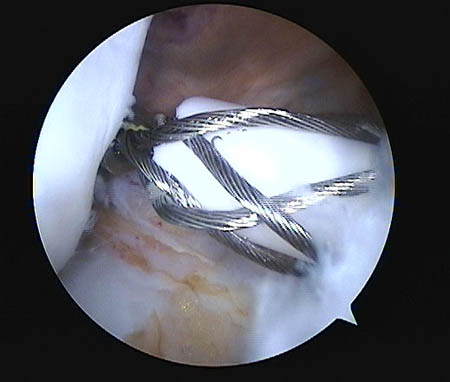

Respecto a su morfología usamos la clasificación de Lage et al.28 (Figs. 9, 10 y 11) que se distribuyeron de la siguiente manera:

-

58.6% Colgajo radial.

26.1% Fibrilada.

14.2% Longitudinal periférica.

1.1% Inestables.

Figura 9: Lesión labral fibrilar.